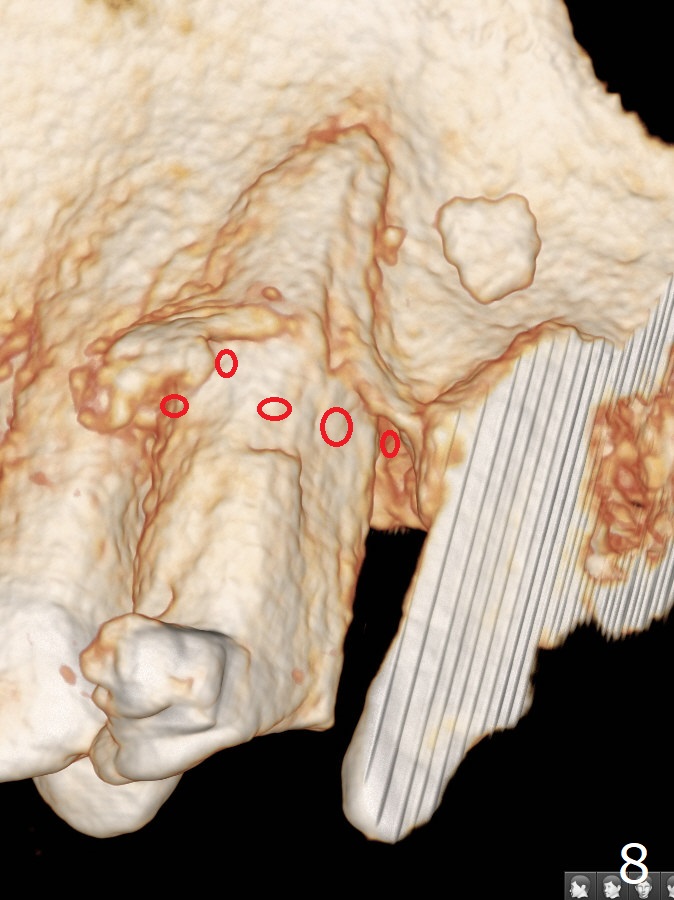

A 62-year-old man had traumatic root fracture at #6 in his teen. The tooth remained asymptomatic until his fifties. Following root canal therapy (Fig.1), the tooth is orthodontically extruded (~ 5 years, Fig.2 (*: bracket)) with apparent disappearance of the infection. The bone distal to #7 seems to increase in height (Fig.3, as compared to Fig.1) and in density (Fig.4). Bone graft could be placed for regeneration with PRF or GEM21S (Fig.5 red (between #6 and 7), pink (buccal to #7 or coronal to the fracture line) circles). With extrusion, the oblique fracture line is more than half or two third supragingival (Fig.6). In spite of severe bone loss, exostosis is present (Fig.7 (mesiobuccal view) E) so that bone graft could be placed palatal to it (Fig.8 red). In case the tooth is non-salvageable, immediate implant will be placed with guide (Fig.9,10). Move lingual button as apical as possible (Fig.12) and make occlusal clearance. Continue extrusion until all of the crack is exposed without deep pocket.